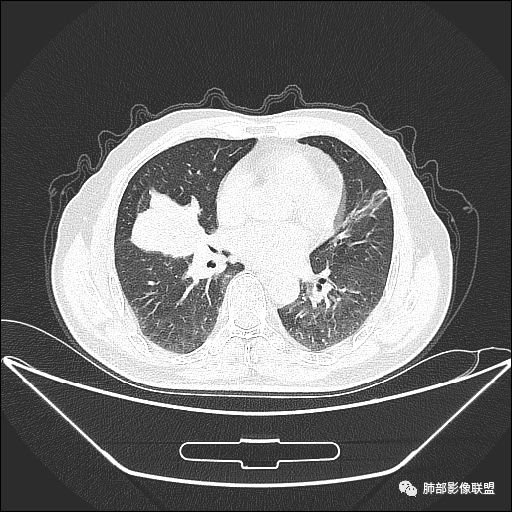

入院CT

老年男性,因“咳嗽咳痰1月余。”入院。病程中咳嗽咳痰,咳黄白痰,间断咯少许鲜红色痰血。PPD阳性。胸CT:右肺中叶外侧段支气管管腔阻塞,大片实性病变,病灶边缘光滑,部分边缘膨隆,可见分叶,肺门及纵隔可见肿大淋巴结,并可见钙化。增强可见病灶明显强化,而且延迟强化明显,病灶内多发低密度区,内见血管影,血管变细、部分血管破坏。考虑恶性病变可能性大,鉴别慢性肉芽肿性病变。

右肺中叶外侧段管腔阻塞、实性病变,病灶边缘光滑,可见分叶,肺门及纵隔可见肿大淋巴结,并可见钙化。增强可见病灶内多发低密度区。

老年男性,咳嗽、咳痰1月余,间断血痰。PPD阳性。

胸CT:跨叶大肿块,主体在中叶,右中叶外侧段支气管阻塞,病灶部分边缘膨隆,可见分叶,部分边缘平直,肺门及纵隔可见肿大淋巴结。增强病灶不均匀强化,延迟强化明显,病灶内多发低密度区,内见血管飘浮,部分血管变细、模糊。考虑:恶性病变可能性大,大细胞?淋巴瘤?鉴别慢性肉芽肿性病变。

右肺中叶软组织肿块,外围向内生长,叶间胸膜向前内移位,肿块近肺门侧跨叶,中叶外侧段支气管截断,密度不均匀,双侧肺门及隆突下见肿大淋巴结,增强后呈中度不均质强化,肺动脉供血,多发坏死区,边界尚清,坏死区域内见结构,结合病史考虑恶性,鉴别诊断1结核,爬行征是沿支气管树分布,外宽,内窄,周围有卫星灶,内气管狭窄后扩张,此例沿叶间胸膜长轴分布,气管有截断,不典型。2炎性肉芽肿,符合的地方下方层面增强后延迟性轻度环形强化,不符临床无发热等急性感染病史,实验室指标不符,病灶周围渗出及慢性炎性改变有,不明显。